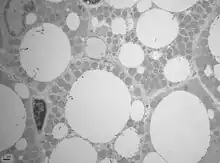

Les adipocytes bruns multiloculaires sont moins nombreux chez l'adulte que les adipocytes blancs uniloculaires. Contrairement à ces derniers qui ont un noyau repoussé à une extrémité de la cellule par la vacuole lipidique unique contenant du triacylglycérol, les adipocytes multiloculaires possèdent un noyau central.

Les vacuoles sont de taille variable. On dénote beaucoup de mitochondries ainsi qu'une riche vascularisation. La couleur brune quant à elle s'explique par la présence de fer au niveau de la matrice des mitochondries.

Le tissu adipeux brun possède une morphologie pseudoglandulaire. L'innervation est assurée par le système nerveux sympathique adrénergique.